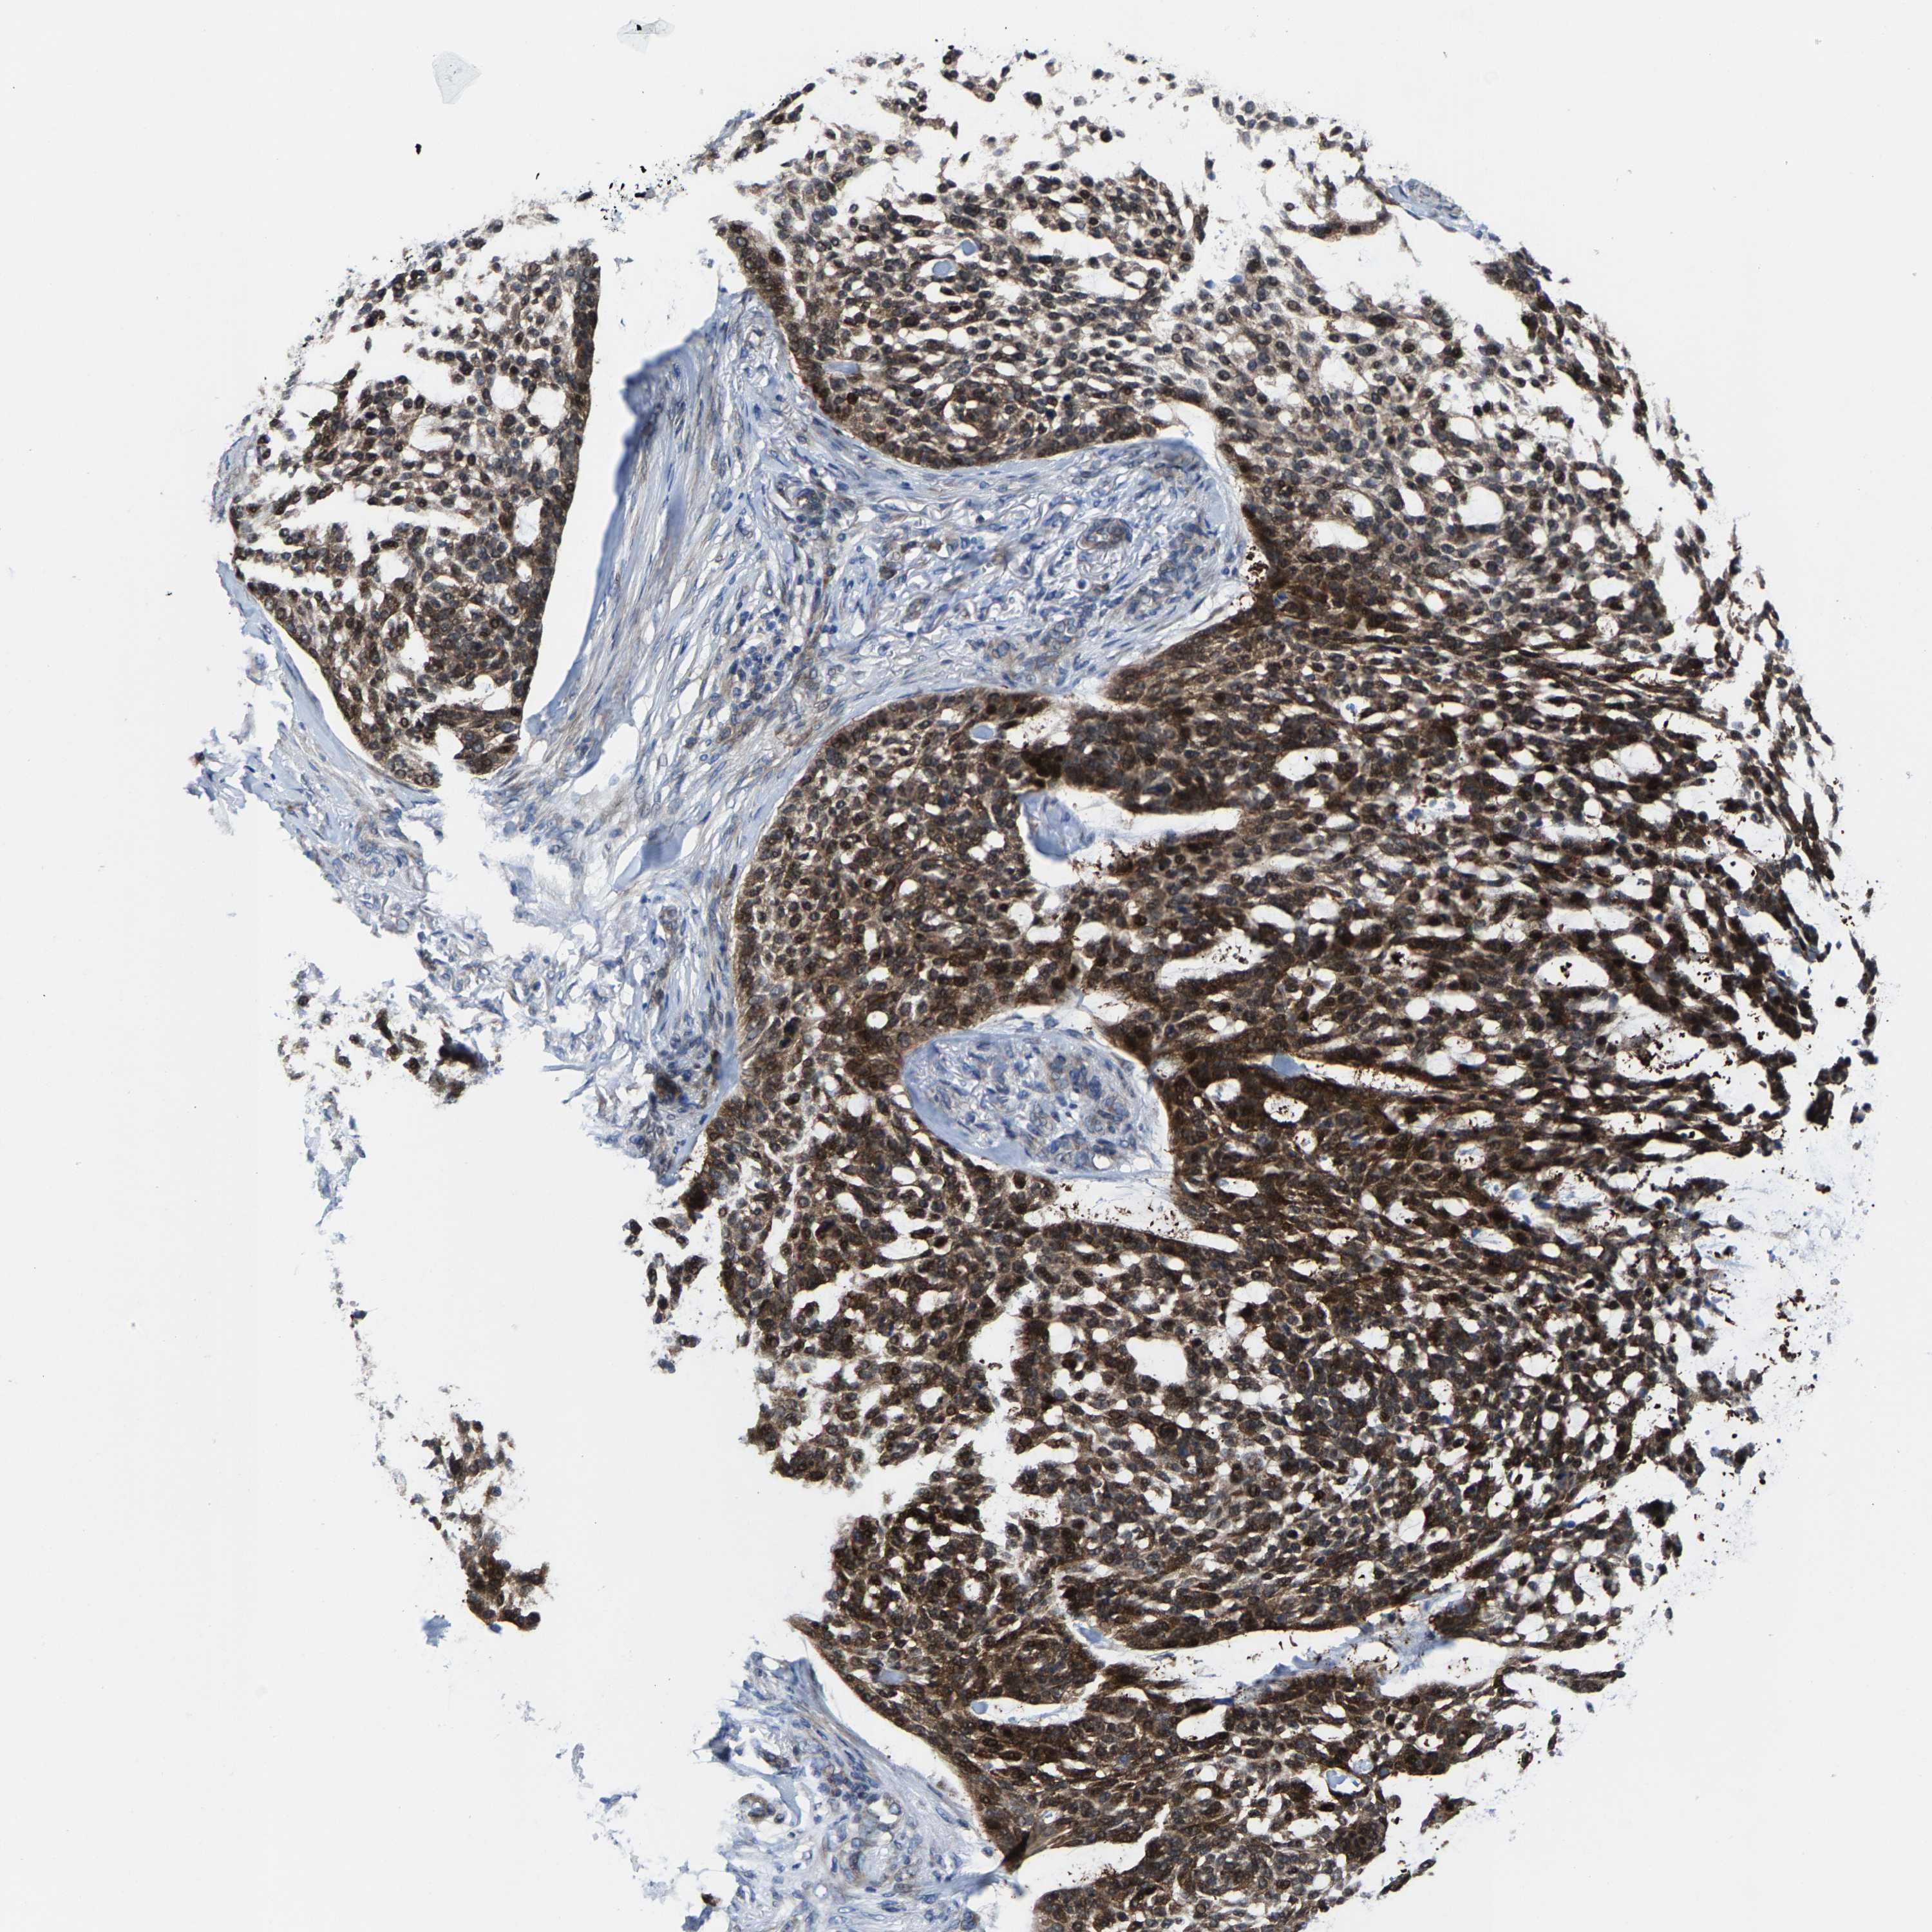

SKIN CANCER - Protein expressioni

A mouse-over function shows sample information and annotation data. Click on an image to view it in a full screen mode. Samples can be filtered based on level of antibody staining by selecting one or several of the following categories: high, medium, low and not detected. The assay and annotation is described here.

Antibody stainingi

Antibody staining in the annotated cell types in the current human tissue is reported as not detected, low, medium, or high, based on conventional immunohistochemistry profiling in selected tissues. This score is based on the combination of the staining intensity and fraction of stained cells.

Each image is clickable and will lead to virtual microscopy that enables deeper exploration of all samples and also displays staining intensity scores, fraction scores and subcellular localization as well as patient and tissue information for each sample.

Antibody HPA020960

Basal cell carcinoma